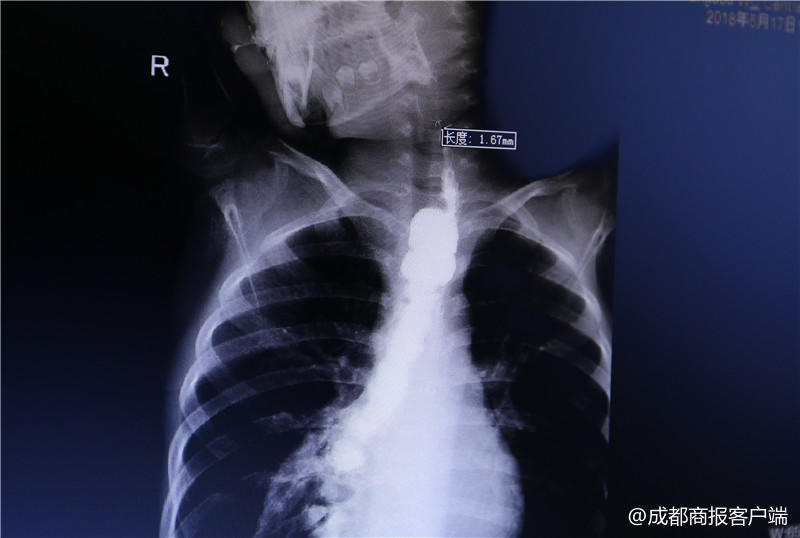

今年4月初,李中贵发现琳琳吃饭的速度越来越慢,而且容易被呛到,于是,李中贵带着琳琳又一次来到成都市妇女儿童中心医院,做了一次检查,发现食道狭窄。5月,琳琳被收治入院。“在门诊做了一个造影,发现食道有狭窄,最窄的地方只有1.8毫米。”琳琳的主治医生、儿外一病区仲铀医生介绍说,琳琳的情况不容轻视。

“挛缩的部位在第4颈椎和第7颈椎位置之间,大约有5厘米长。”赵虎介绍说,检查结果发现,琳琳结肠再造的食道挛缩严重,进食通道十分狭窄,最窄的位置只有1.8毫米。